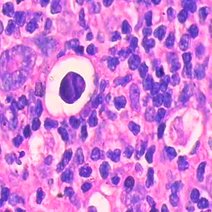

囊肿是什么

囊肿是指具有囊腔结构,外有囊壁,内有液体或其他成分的囊样结构,是一种良性疾病。人体多个器官或组织均可发生,位于真皮及皮下组织的表皮囊肿、皮样囊肿;位于内脏...32124人收听